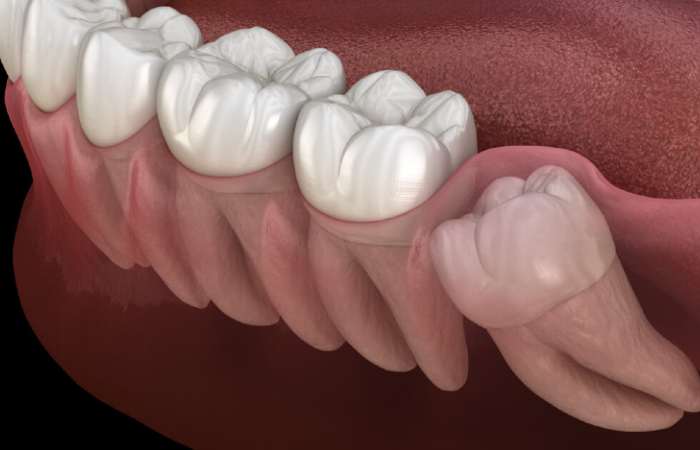

Oral surgery includes the removal of impacted and buried teeth or roots that your own general dentist may not be able to treat.

Our oral surgeons use modern minimally traumatic techniques to remove teeth safely with optimum healing times.

Yes we remove impacted teeth.